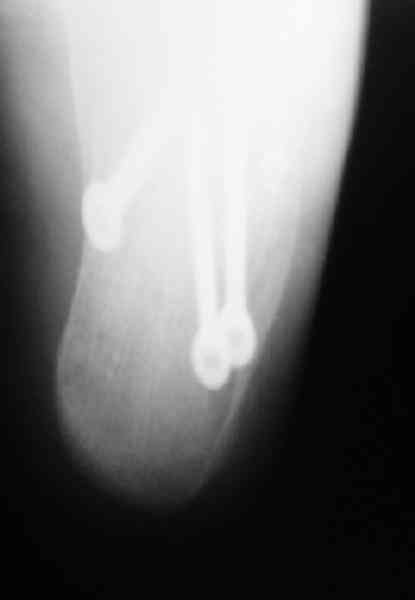

Re: Перелом пяточной кости

Открытый и закрытый способы лечения.